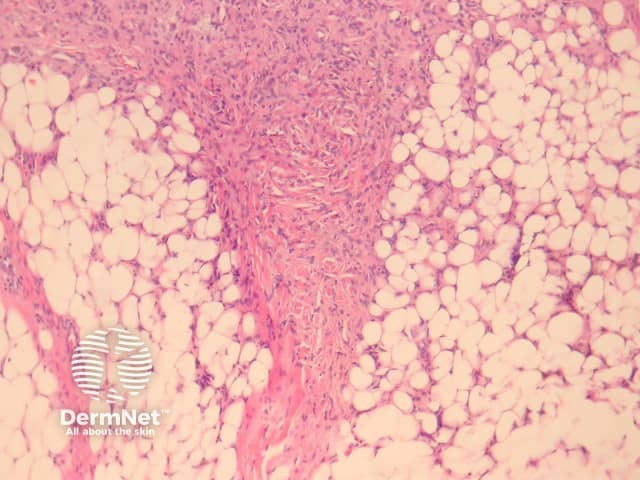

Dermatofibromas are dermal tumours characterised by a poorly defined proliferation of fibrohistiocytic cells within the dermis with an overlying grenz zone of sparing (figure 1). At the periphery of the lesion, there is entrapment of collagen (figure 2). The overlying epidermis may be acanthotic with increased basal layer pigmentation. Sometimes there is basaloid induction of the epidermis (figure 1, arrow) which may resemble small basal cell carcinoma or benign follicular tumours.

Figure 1

Figure 2